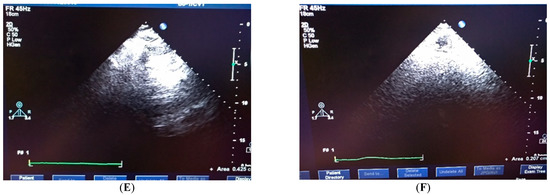

4.4. Clinical Testification